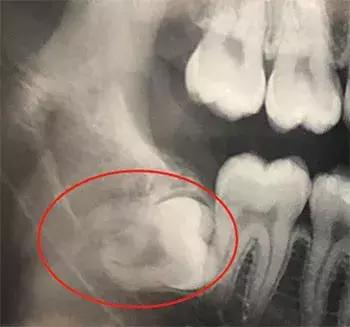

但如果反复疼痛,出现阻生情况比如前倾、后倾、水平、倒置等现象的,这样的智齿最好还是拔掉,因为它是没法长正了,而且还可能侵及、积压邻牙,前牙还可能有“报废”的风险。

刘医生说,这个需要拍个全口片再下定论。

如果智齿已经正常萌出,且位置、方向都正常,与对颌牙有很好的咬合关系,没有发炎疼痛史,也没有龋坏的,那么就可以将其保留。